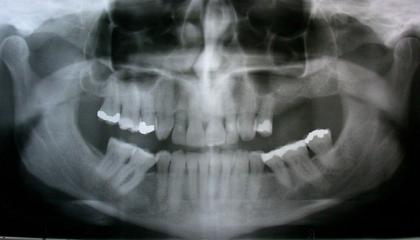

Dental Implants

There is no question that dental implants have revolutionized tooth replacement and the practice of dentistry. Today’s highly successful dental implants consist of an artificial tooth root, to which a crown is attached. This system looks just like the natural teeth in your mouth when you smile: there is no visible difference. In addition, Implants do not decay and are relatively free from developing gum disease.

The practice of implant dentistry requires expertise in planning, surgical placement and crown fabrication: it is as much about art and experience as it is about science. It also requires teamwork between you and your dentist, and implant surgeon, and a dental technician.